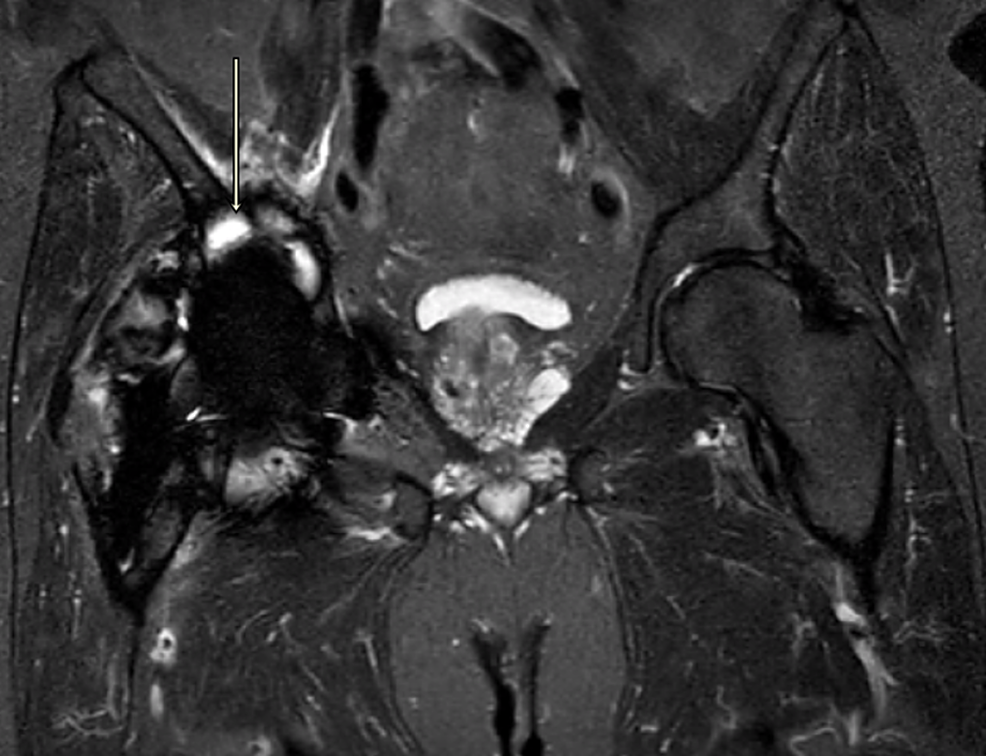

From www.cureus.com

Cureus A Case Report and Literature Review to Aid in the Management Trunnionosis Symptoms While contributing elements may include. — symptoms should first raise suspicion in order to diagnose a patient with trunnionosis. — a wide range of signs and symptoms have been described for trunnionosis. — symptoms of systemic toxicity include neurological (peripheral numbness, memory loss, and cognitive changes),. — tha trunnionosis is a complication of hip arthroplasty caused. Trunnionosis Symptoms.